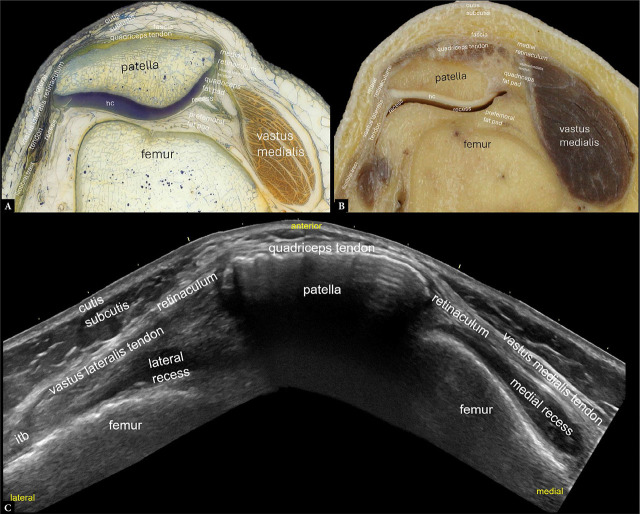

Purpose: To provide an overview of the normal anatomy of the knee using high-resolution ultrasonography.

Materials and methods: Normal ultrasound images were obtained from a healthy subject, and corresponding images of human anatomy and histology were acquired from body donors.

Results: Several high-resolution ultrasound, anatomical, and histological images were created to illustrate and comprehensively describe the basic standard scans in compliance with international standards. This atlas summarizes a selection of typical normal findings.

Conclusions: This overview explains the normal anatomy of the knee as seen by ultrasonography. High-resolution knee musculoskeletal ultrasonography aims to provide an accurate structural evaluation, which requires comprehensive knowledge of sonoanatomy. When used appropriately, contemporary high-resolution musculoskeletal ultrasonography enhances knee imaging by connecting anatomical cross-sections and intricate histology to specific anatomical features.